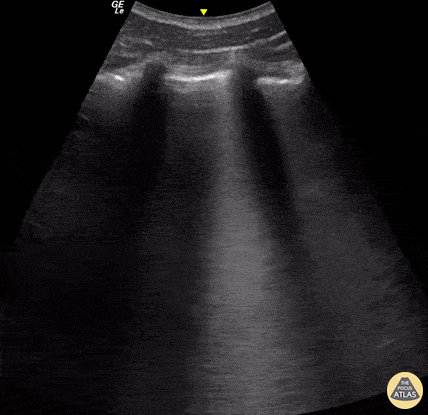

A 23-year-old male was admitted to the ED following a motorcycle accident. He subjectively reported dyspnea; objectively was hypoxic. POCUS seen here (obtained from L3 zone using curvilinear probe) reveals multifocal B-lines consistent with pulmonary contusion. This case illustrates that bedside US is useful beyond diagnosing pneumothorax and hemothorax in trauma patients. Renato Tambelli, Emergency Physician Hospital das Clínicas de Marília, Brazil. @R_Tambelli / @JediPocus